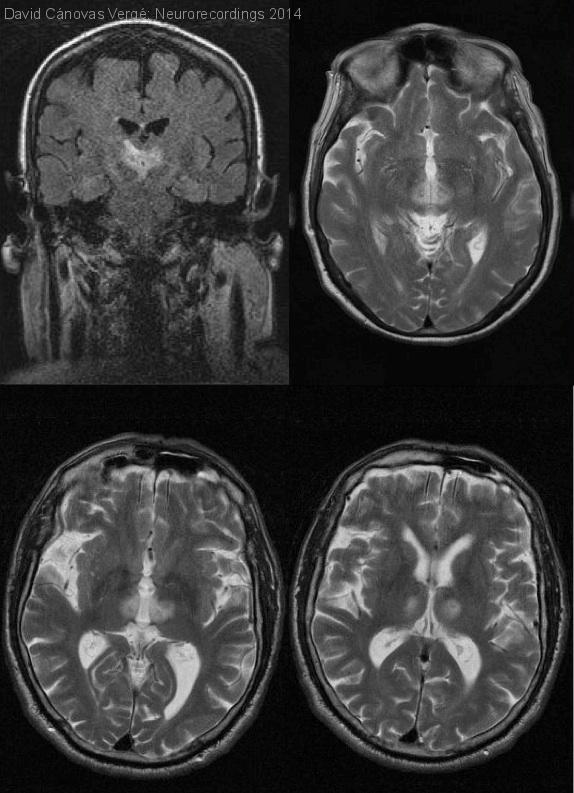

Infarto talámico de la arteria de Percherón

Diagnóstico final: Infarto talámico paramedial bilateral

Neurología: Patología cerebrovascular

Etiología: Ictus